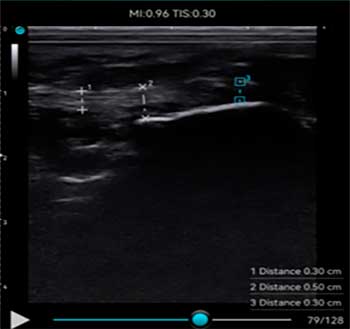

La utilización de un ecógrafo para diagnosticar la fasciosis plantar es esencial y es la herramienta más idónea para su examen.

En ecografía observamos una señal hipoecoica con separación de las fibras de la fascia plantar. El valor normal de fascia plantar sana es de 3mm. Es importante realizar un estudio ecográfico comparativo en el otro pie para visualizar el rango de grosor de la otra fascia.

A continuación adjunto varios casos de imágenes ecográficas con fasciopatía plantar: